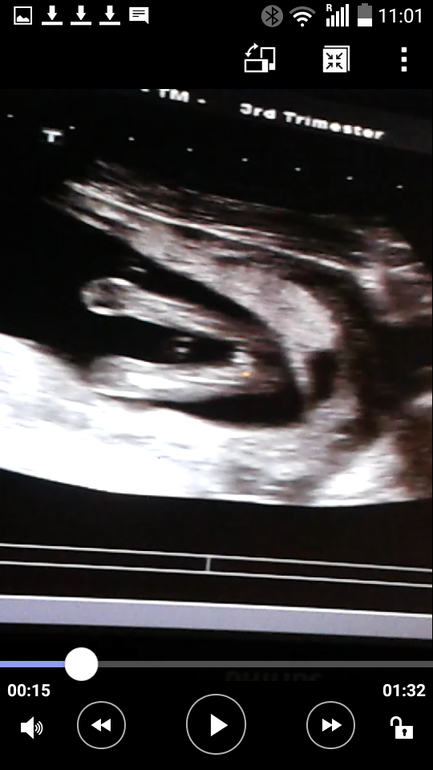

Вертится с трудом, но видно всё было четко. Несколько раз поймали ракурс и все рассмотрели.

Срок 16 недель.

между ножек:

А это мы на сроке 16,5)) Нам Мальчика пообещали)) Теперь Смотрю на Ваши фотки и точно понимаю что к чему)))